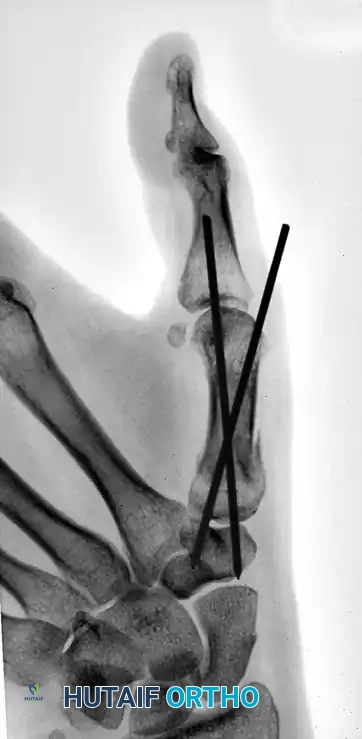

Sometimes, more than one Kirschner wire is required to achieve absolute rotational stability. Depending on the fracture geometry, the secondary wire may engage carpal bones other than the trapezium (such as the trapezoid or the capitate) for adequate fixation.

The following sequence illustrates the progression from injury to successful closed reduction and K-wire fixation into the trapezium: